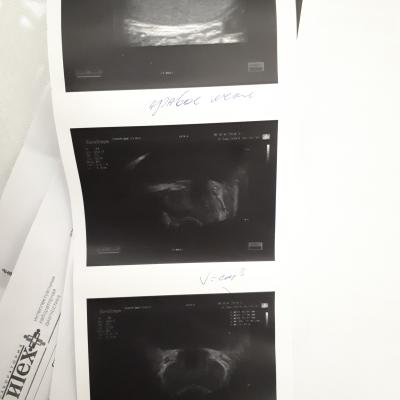

Здравствуйте ! месяц назад почувствовал резкую боль в правом боку, было подозрение на аппендицит (не подтвердилось) вместе с этой болью заболело правое яичко. Обратился к врачу сделал обследование пролечился не помогло боли остались. Обратился к другому урологу, он провел обследование назначил лечение. Вопрос правильный ли диагноз и назначенное лечение? (все обследования на фото)